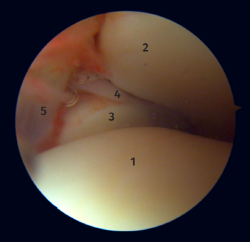

Anatomía artroscópica del complejo medial

Mediante la artroscopia podremos ver las fibras profundas del ligamento deltoideo, que es la porción intraarticular del ligamento. Medial y proximalmente a la punta del maléolo ya tenemos la inserción de la capa profunda del ligamento deltoideo. Si no hay lesión, veremos la porción anterior de las fibras tibioastragalinas profundas. Cuando existe una lesión de estas, podemos visualizar la porción intermedia y posterior. Las bandas superficiales, por su ubicación más externa, no son visibles mediante artroscopia, a no ser que no exista una lesión de las profundas (Figura 5).

Figura 5. A: visión anterior del receso medial del tobillo; B: con el palpador tensamos las fibras del ligamento tibiotalar profundo.